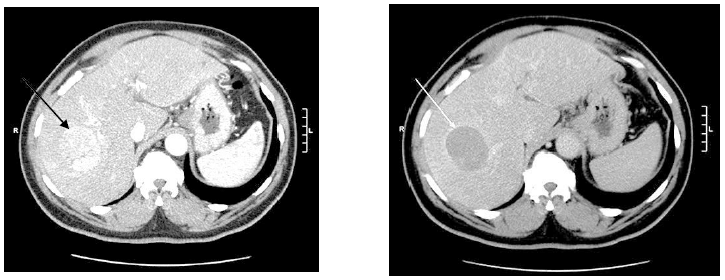

Homem de 63 anos, com história de cirrose por hepatite viral C, apresenta em exame de rotina três nódulos hepáticos que têm as mesmas características de realce à tomografia de abdome trifásica, dois deles no lobo esquerdo e um no direito. Essas lesões medem 2,1 cm, 2,3 cm e 4,7 cm, estando esta última representada no exame abaixo. Não há sinais tomográficos de trombose portal ou acometimento extra-hepático. Seu escore de Child é A (6 pontos), e seu Performance Status é 0. Sobre esse caso clínico, assinale a alternativa correta entre as abaixo.